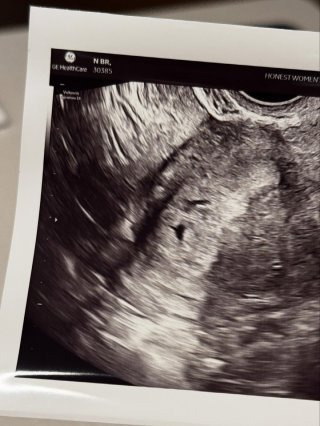

현재 임신 8개월차에 접어든 남보라는 오는 6월 출산을 앞두고 있다. 태명 ‘콩알이’의 초음파 사진을 공개하며 설렘을 공유했고, 태교 방법으로 뷔 사진을 보며 긍정적인 마음을 유지하고 있다고 전했다. 방송 활동도 이어가며 건강한 모습을 보여주고 있으며, 육아 경험이 풍부한 장녀답게 자신감 있는 모습을 드러냈다.